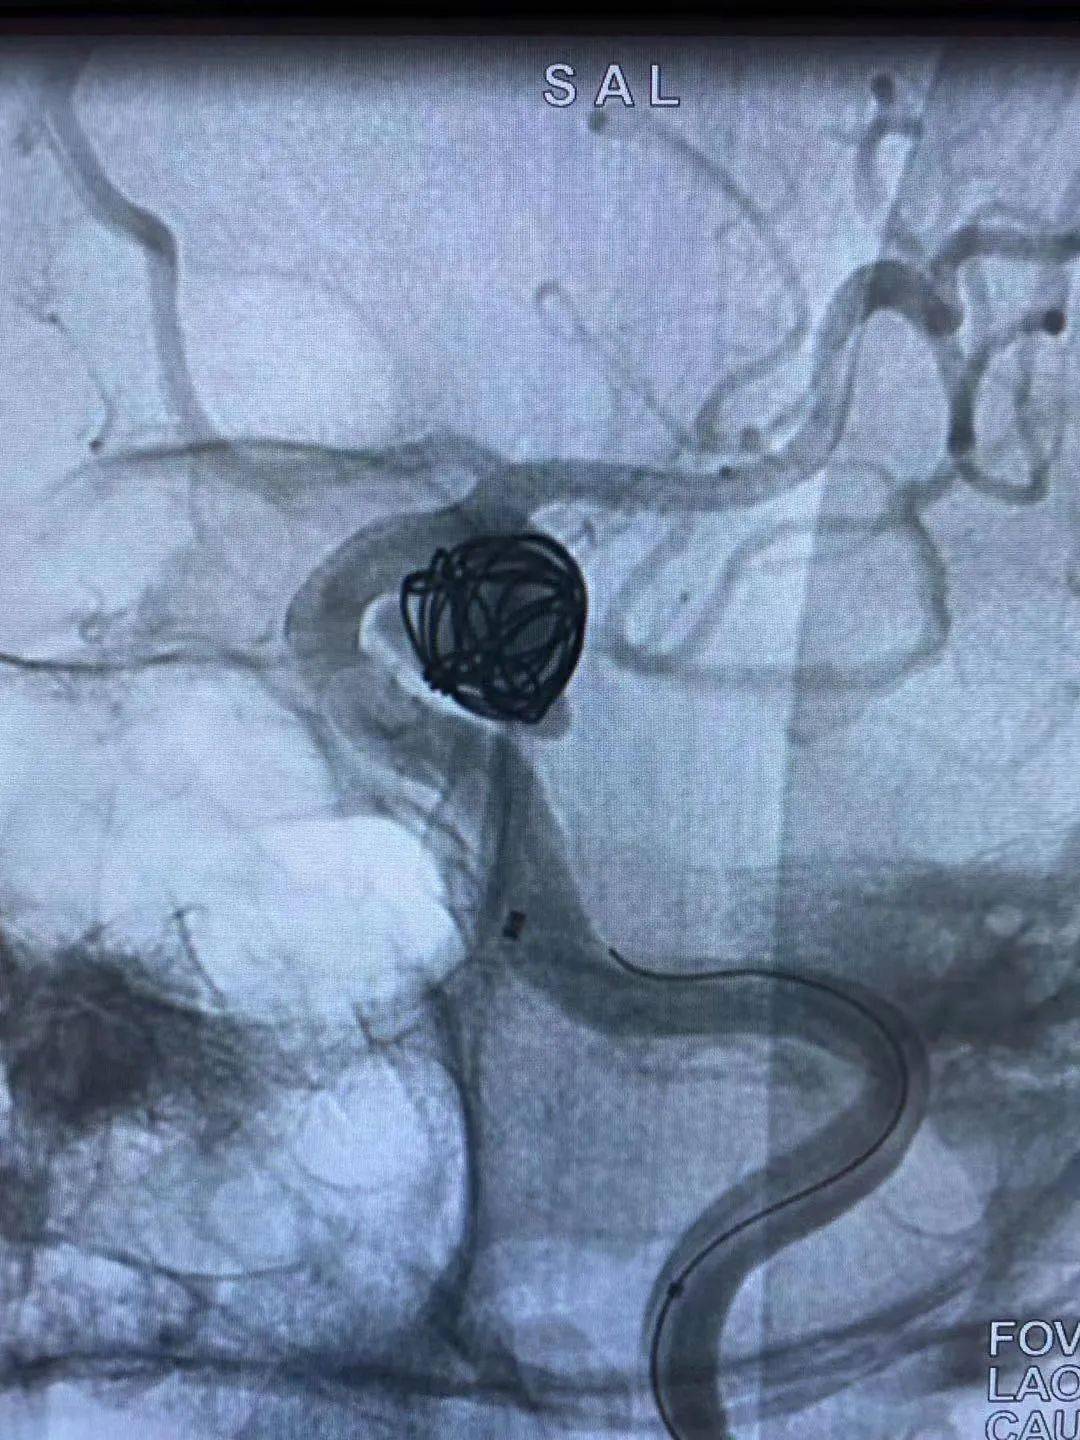

动脉瘤的神经介入治疗主要产品是弹簧圈和密网支架.

中枢介入第188期可原位释放的编织支架leo支架辅助动脉瘤栓塞的操作